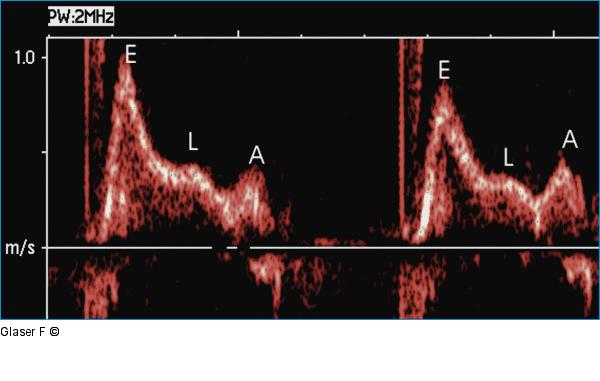

Abbildung 3: Gepulster Doppler - Mitraldoppler Gepulster Doppler - Mitralklappe: Restriktives Flußprofil mit hoher E-Welle, rascher Dezeleration der E-Welle, E/A-Amplitude > 2 und Zeichen der verzögerten myokardialen Relaxation (L-Welle) im Anschluß an die E-Welle. |

Abbildung 3: Gepulster Doppler - Mitraldoppler

Gepulster Doppler - Mitralklappe: Restriktives Flußprofil mit hoher E-Welle, rascher Dezeleration der E-Welle, E/A-Amplitude > 2 und Zeichen der verzögerten myokardialen Relaxation (L-Welle) im Anschluß an die E-Welle. |